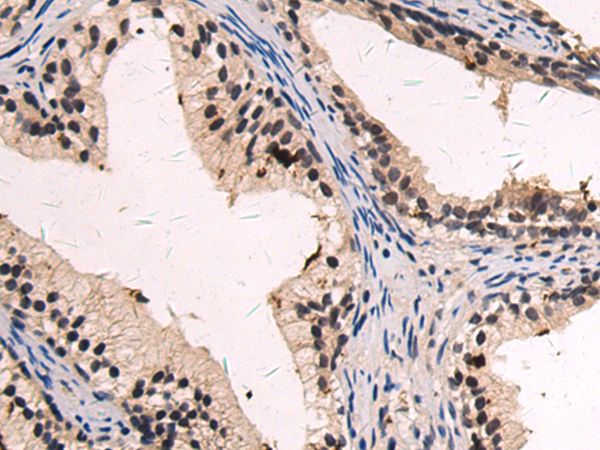

分类: 科研抗体货号: P09795别名: MCAK; CT139; KNSL6应用: IHC反应种属: Human, Mouse, Rat